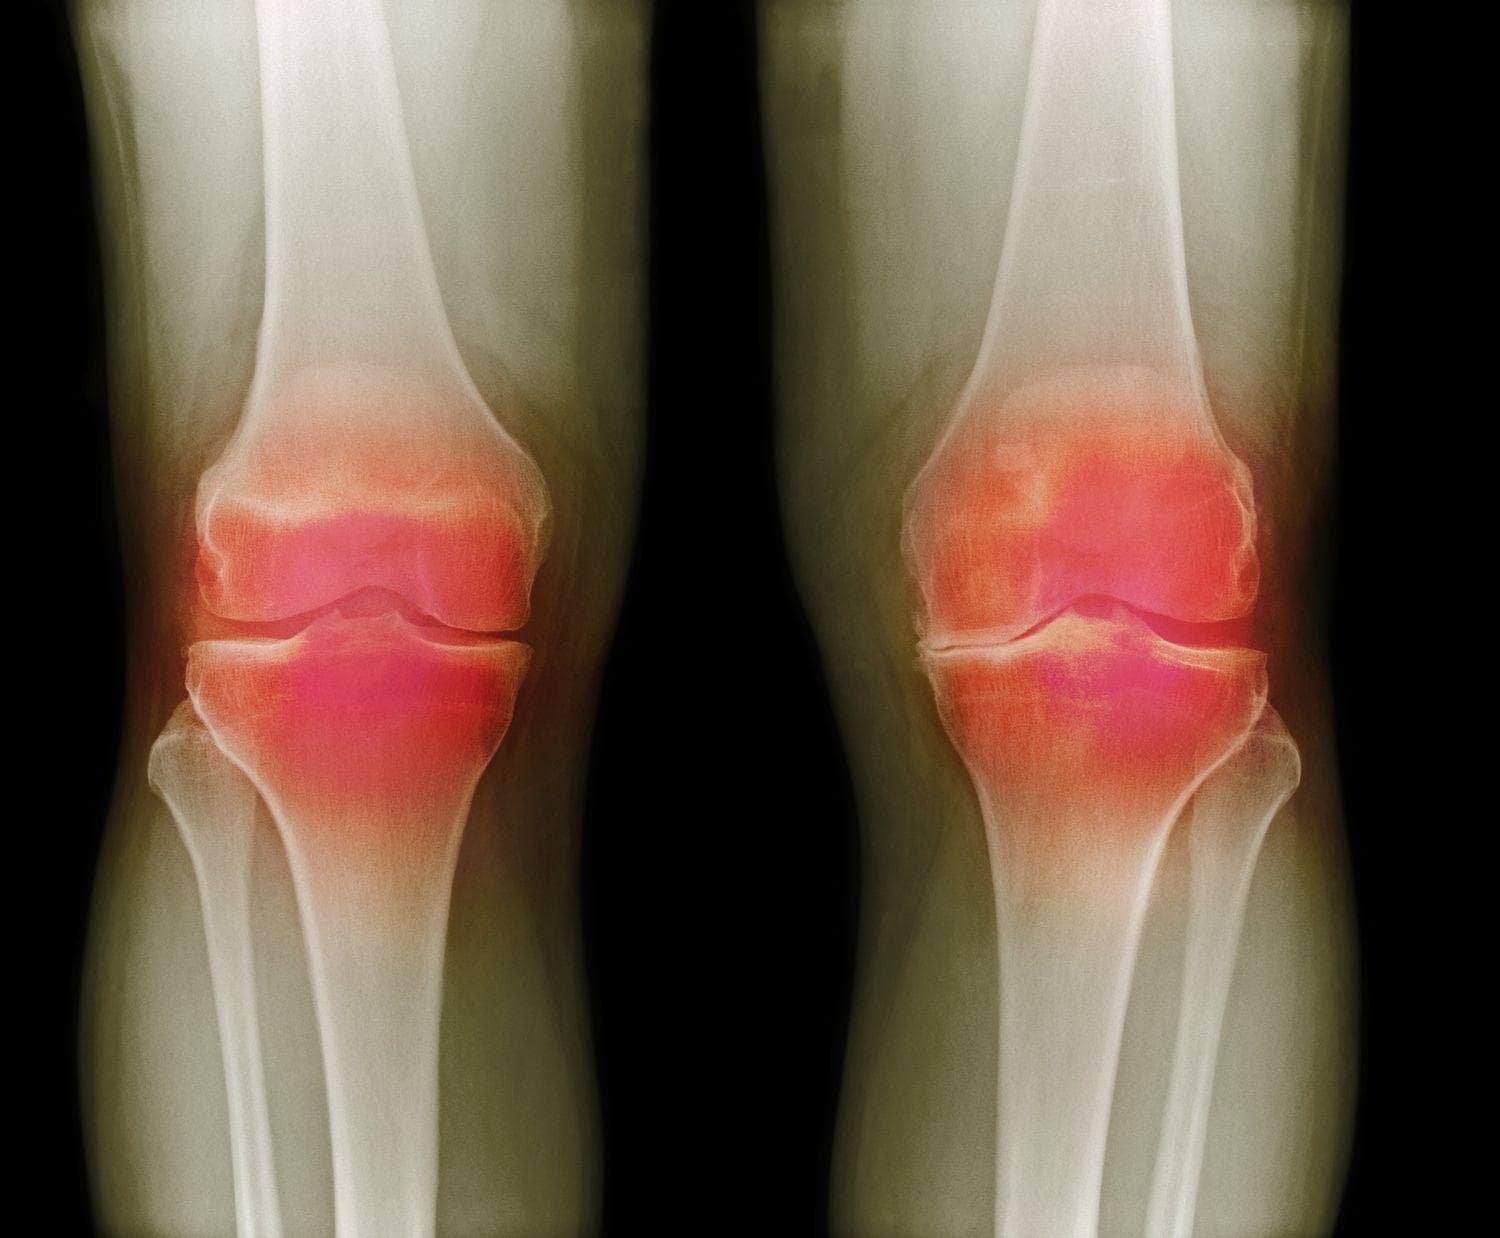

Artróza (degenerace chrupavky) patří mezi nejčastější příčiny bolesti kloubů a pro mnoho lidí představuje velký strašák. Nejčastěji se řeší například artróza kolene, kyčle nebo ramene. Dnes už ale víme, že i s artrózou lze vést kvalitní a aktivní život. Problémem je spíše množství mýtů a polopravd, které kolem artrózy kolují a zbytečně lidi omezují. Pojďme si tuto komplexní problematiku zjednodušit pomocí několika mýtů a faktů.

Co je artróza a proč vzniká?